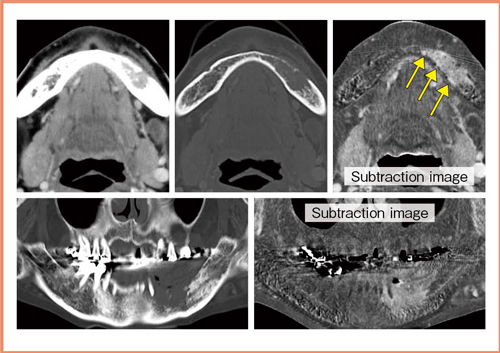

Aquilion ONEによるサブトラクション法は,最初に患者さんの頭や下顎をしっかり固定し,造影開始後,7秒(plain画像)と60秒(腫瘍濃染画像)の2回Volume Scanを行う。得られた2つのデータをサブトラクションすることで,骨皮質が除去され,造影剤により増強された領域のみ強調された画像(Subtraction Image)を取得することができる(図1)。

特に,下歯肉がんにおける術前画像診断は術式の決定に必須であるが,もう1つの重要な役割として,顎骨切除の範囲設定がある。骨の切除断端は,術中迅速組織検査が行えないために,画像による術前評価が唯一の判断材料となり,その責任は重い。従来,下歯肉がんではCTとMRIの両方を施行し,CTでは骨の破壊程度を観察していた。ここにサブトラクション画像を追加することで,骨髄に腫瘍がどのように進展しているかを,皮質骨の情報と共に確認することができる(図4)。造影MRIに加え,CTのサブトラクション画像や骨条件の画像などと総合的に評価することで,より正確な下顎骨浸潤の術前評価が可能になったと実感している。

図4 サブトラクション画像による術前画像評価